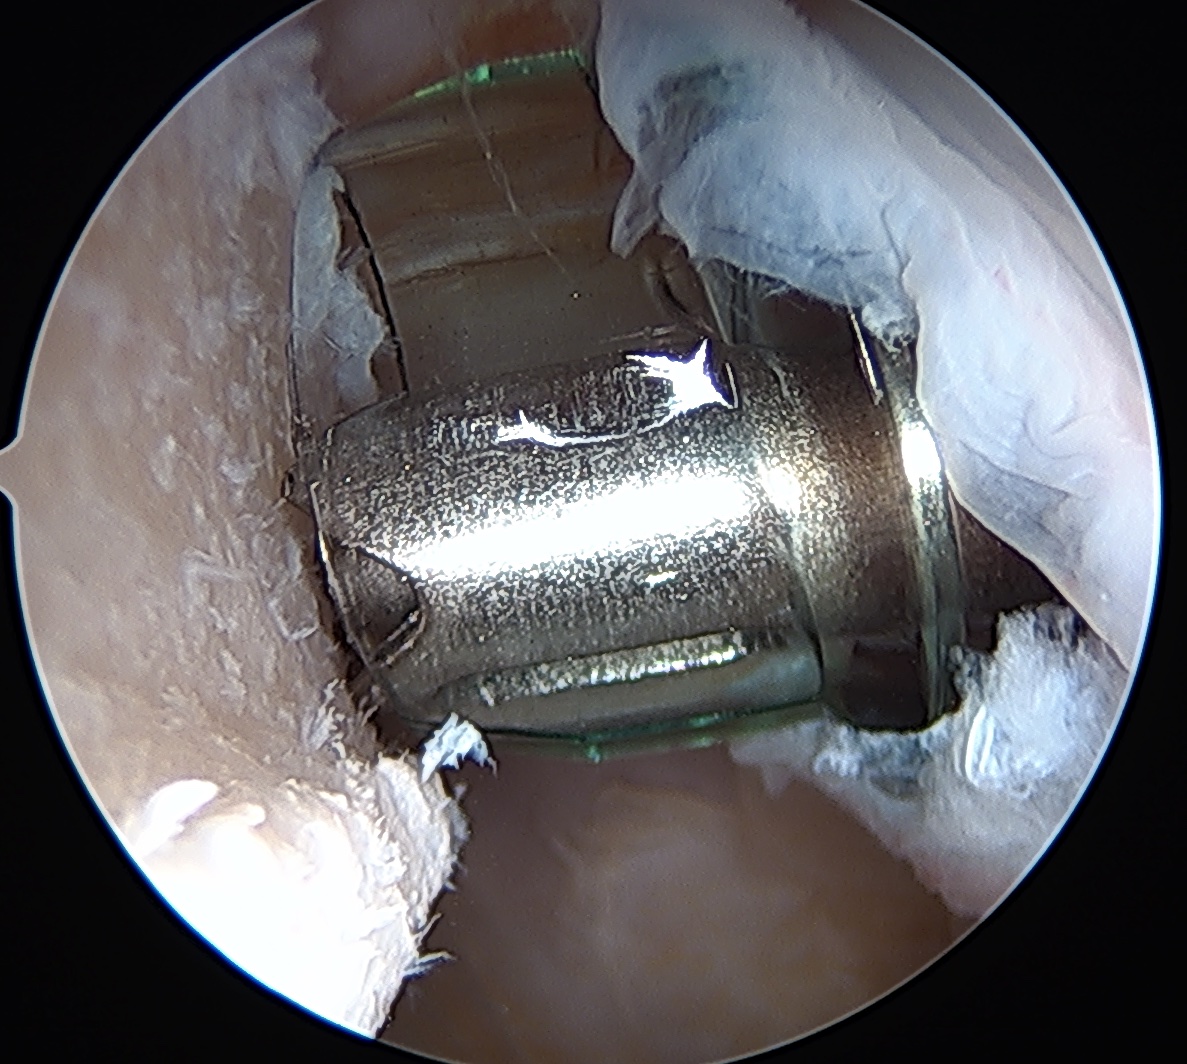

Anchor insertion into Hill Sachs lesion